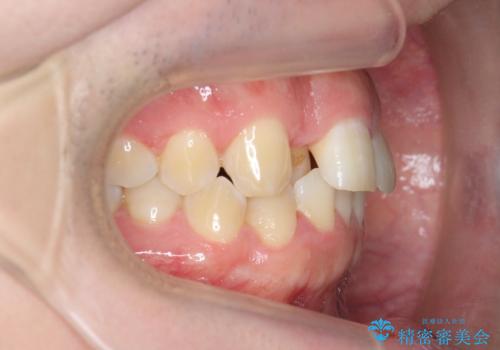

前歯が隠れていて見えない クロスバイトの矯正治療

- 「前歯が1本隠れていて見えない、歯並びを矯正治療で改善したい。」と希望され来院されました。

奥に隠れている前歯を並べられるスペースを確保したのち、歯並びを整えていきます。

前歯のスペース不足により1本だけ後方に位置している状態でしたが、しっかりとスペースを確保し配列することができました。